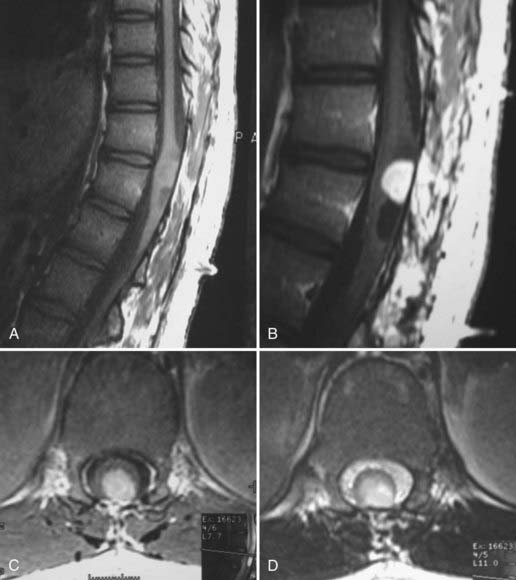

脊髓肿瘤 约占中枢神经系统肿瘤的15%,大多数硬膜内肿瘤起源于脊髓和终丝、神经根或脑膜的细胞成分。脊柱硬膜内腔的转移很少表现为肿块病变。硬膜内脊髓肿瘤是根据其与脊髓的关...

脊髓肿瘤 ,也称椎管内肿瘤(intraspinal tumors),是发生于脊髓本身及椎管内与脊髓邻近组织(脊神经根、硬脊膜、脂肪组织、血管、先天性残留组织等)的原发性肿瘤或转移性肿瘤的总...

Constantini检查的儿童中有76例(46%)患有星形细胞瘤,其中18例为恶性肿瘤,58例(35%)为混合性胶质细胞瘤,其中大部分为神经节胶质瘤。Rifkinson-Mann和合著者报告了171例由Epstein手术治疗...